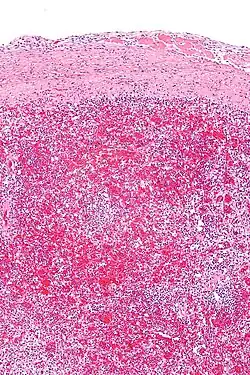

In pathology, hyaloserositis is the coating of an organ with a fibrous hyaline,[1] resulting from inflammation of the serous membrane (serositis) covering the organ.[2]

The spleen is commonly affected and often referred to as sugar-coated spleen.[3] The liver and heart are also sometimes affected and referred to as frosted liver (or sugar-coated liver) and frosted heart respectively.[1]